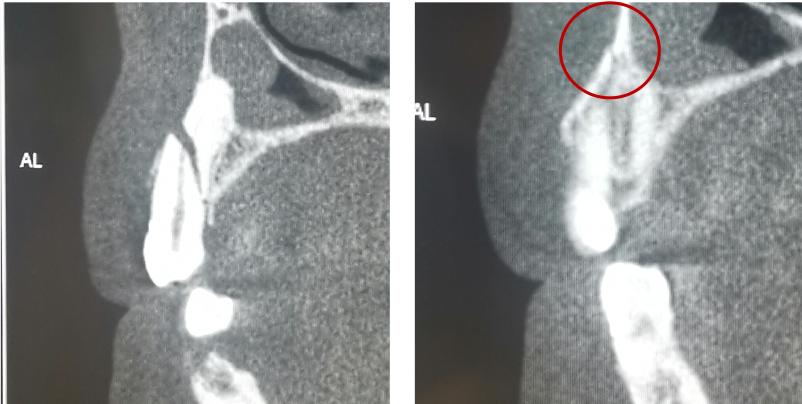

冠根折:累及牙釉质--牙本质--牙骨质折断,累及牙釉质--牙本质--牙骨质--牙髓折断

治疗方案:方案(1)正畸或外科牵引4mm+冠延长+根管治疗+桩核冠修复或根面覆盖;方案(2)拔除患牙后种植修复;方案(3)意向性再植;方案(4)自体牙移植。